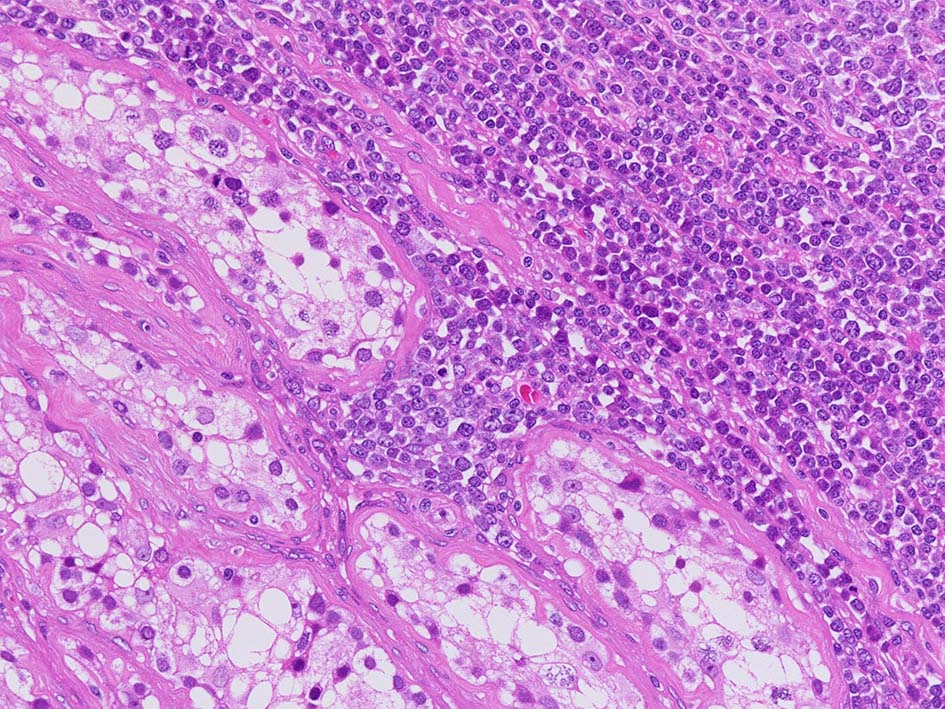

小リンパ球と同程度か1.5倍くらいのサイズ, round/ convoluted nucleiをもつリンパ球がシート状密に増殖する. 核クロマチンは粗で, 核小体が認められる核もある.

DLBCLとは細胞の大きさや細胞所見が異なっている. 精細管への浸潤, 占拠所見がある.